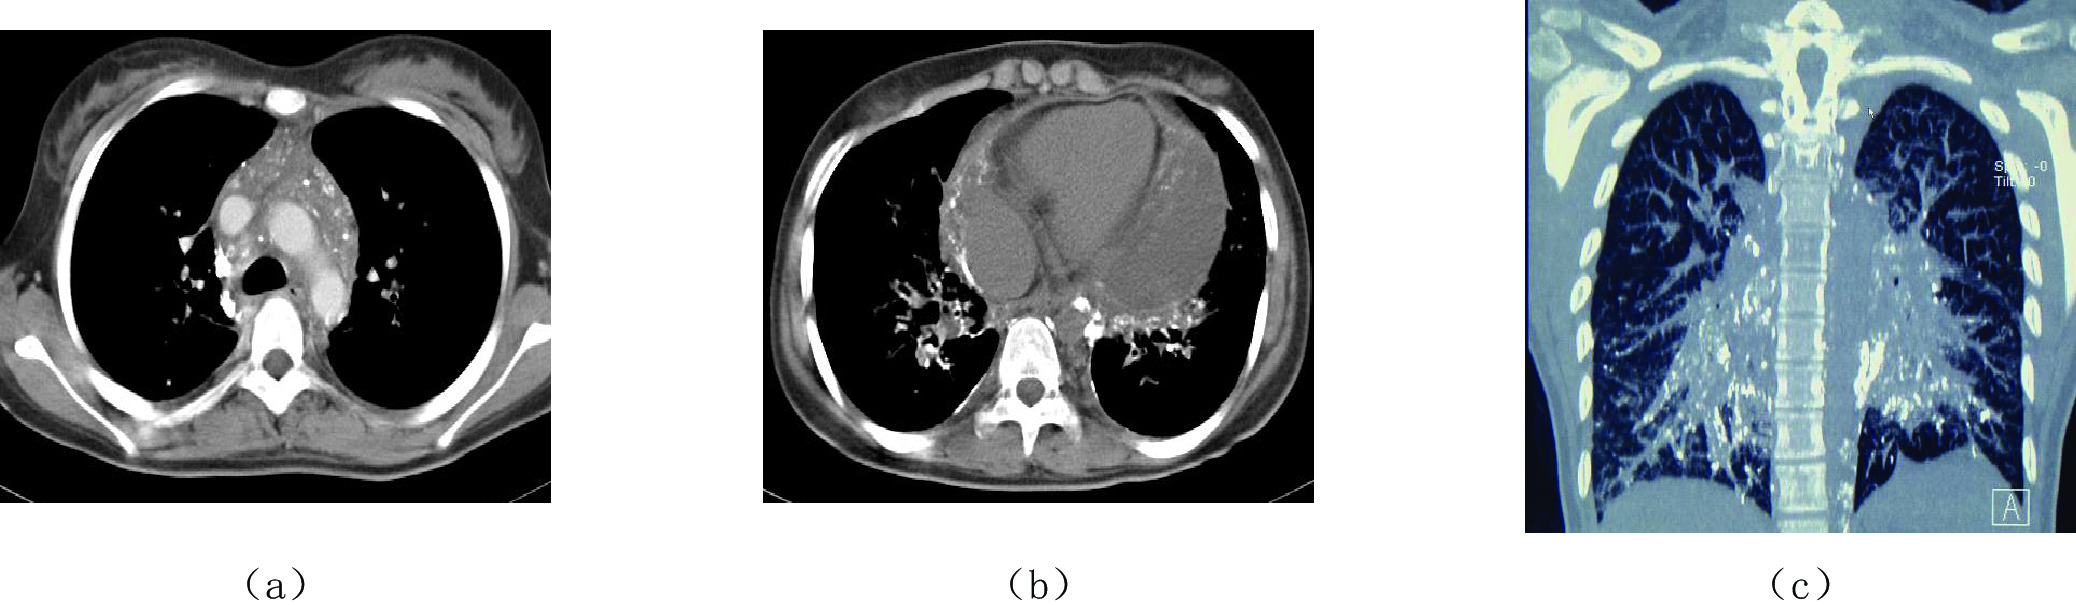

3.2 CT淋巴管造影成像

CT淋巴管造影成像(CT lymphangiography,CTL),是指DLG后30~60 min或延迟(48~72 h)行全身多排螺旋CT扫描(MSCT),扫描范围上缘自锁骨上5 cm处至腹股沟下方5 cm处,扫描后将原始图像传至随机工作站,行MPR、CPR、MIP、SSD及VR等三维重建后处理[6-8]。

CTL是LG后某一个时间段的静止图像,可清晰显示淋巴管内的对比剂回流情况、有无返流或漏出以及病变的部位和程度,同时可显示扫描范围内所有脏器有无相关器质性病变,对于淋巴回流障碍性疾病的定位、定量和定性诊断以及临床分期或分级、疗效评价和风险因素预警等可提供重要的影像学依据。